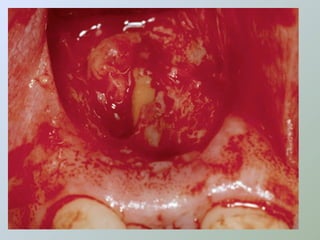

CURETAGEM

O tecido inflamatório em torno do

ápice radicular deve ser removido

para:

• Ganhar acesso e melhorar a

visibilidade

• Obter material para histopatológico

• Reduzir a hemorragia

• Evitar danos aos dentes

adjacentes

• Procurar remover a totalidade da

lesão

• Porção retro-radicular

• Uso de agentes hemostáticos